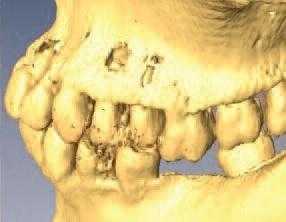

Эндодонто-пародонтальные поражения (ЭПП) - сложная проблема современной стоматологии, так как их диагностика и лечение требуют от врача знаний в области пародонтологии и эндодонтии (рис. 1, 2).

Рис. 2. ЭПП в области зуба 35.